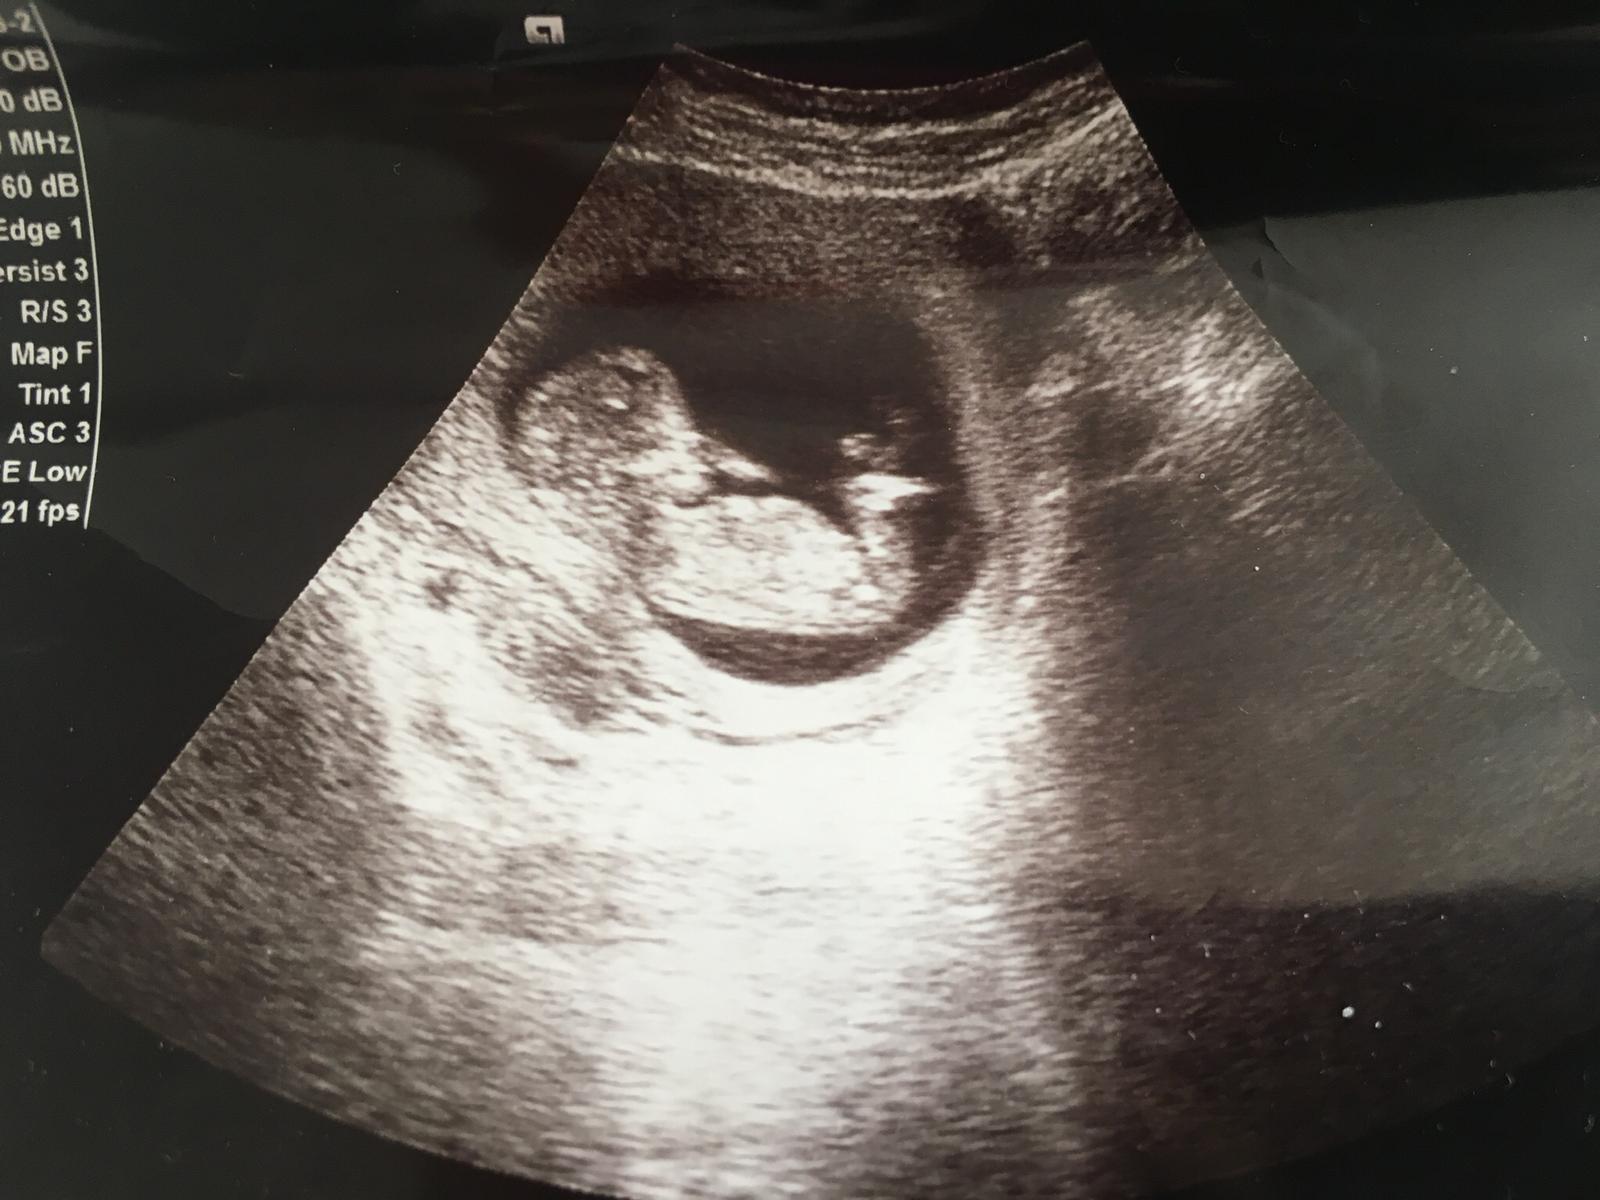

Nub teorisi yanılma payı var mı tutmayanlar var mı ile ilgili Melekler Forum'daki soru şöyle Kızlar 13 haftalık ultrason resmimize göre cinsiyet hakkında yorum yapabilirmisiniz çok merak ediyorum bir de yanılma payı var mı ?

Merhaba arkadaşım, yüklemiş olduğunuz resim ışıktan hayli zarar görmüş . Görseli büyütüp yakınlaştırdım . Tahminime göre emin olmamakla birlikte bebeğinizin cinsiyetinin kız olduğunu düşünüyorum.